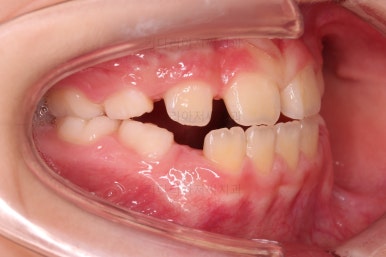

초진 시 입안의 모습입니다.

아래쪽 치열이 전반적으로 윗니보다 앞쪽에 위치한 전형적인 앵글씨 3급 부정교합인데요.

어금니에서부터 앞니까지 아랫니가 윗니보다 앞쪽에 위치하네요.

특히 앞니는 아랫니가 윗니보다 나와있는 "반대교합" 상태였고요.

또한 위아래로 겹침이 없고 떠있는 "개방교합" 상태였어요.

즉, 앵글씨 3급 부정교합 - 반대교합 - 개방교합 등 굉장히 복합적인 교합의 문제를 가진 환자였습니다.